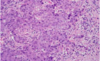

Berätta om invasive duktal bröst cancer

Stora diffenterings skillnader

När cancercellerna växer blir de som sår i vävnaden

Förkalkning är vanligt

Desmoplastisk stroma reaktion

Berätta om Medullär bröst cancer

Pushing growth Allvarliga kärn atypia Tydlig inflammatorisk respons God prognos

Berätta om Invasiv lobulär bröst cancer

Hög diffentering

Ingen atypia

låg proliferation

Karaktäriserand drag ( långa filer eller fasta)